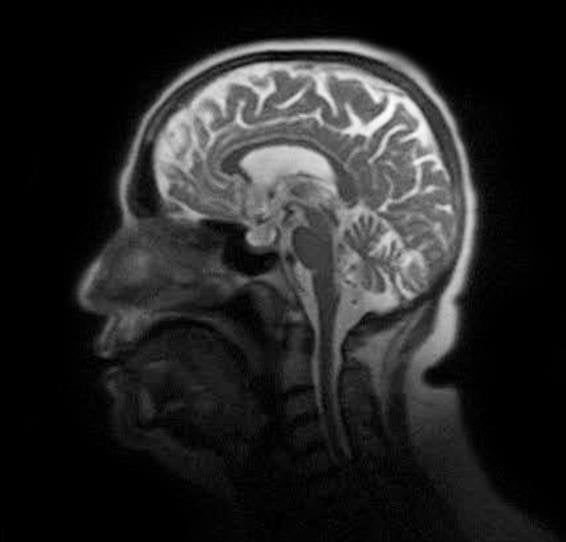

@3DMedico1 Cerebellar Medulloblastoma